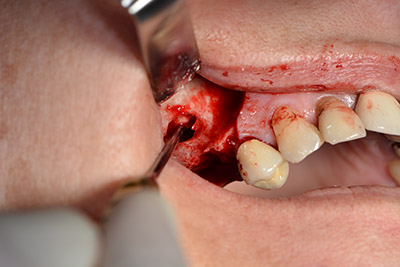

Surgical procedure for implantation

pilot drilling

Image 9: Overview and setting for pilot drilling.

The classic incision (crestal, buccal relief) and the preparation of the mucoperiosteal flap enabled a good overview.

Sky implants (bredent) were used this case. The surgical protocol of these, specify pilot drilling at about 1200 rpm (Fig. 9).